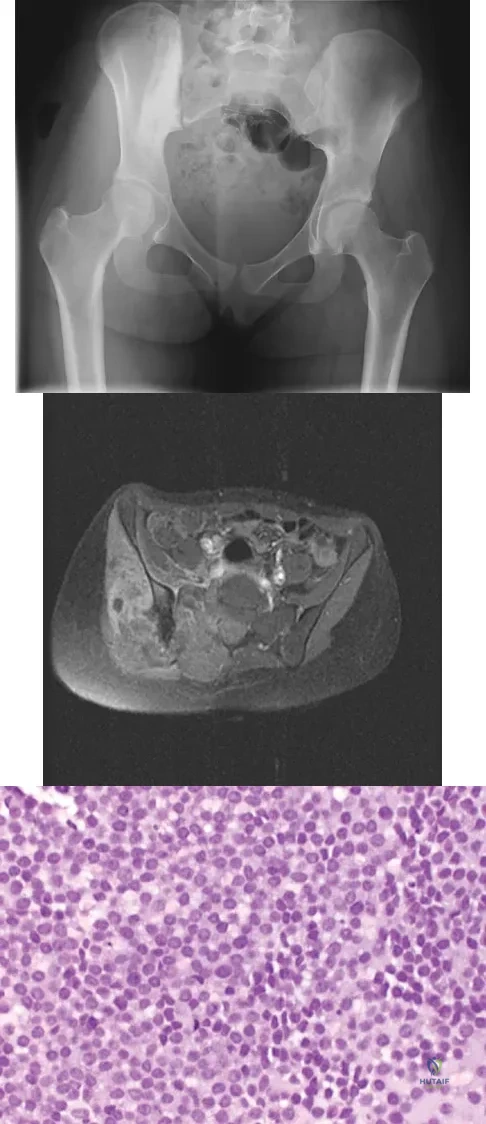

A 43-year-old woman has had pain in the left hip for the past 2 months. A radiograph, CT scan, MRI scan, and biopsy specimens are shown in Figures 16a through 16e. What is the most likely diagnosis?

A 13-year-old girl was riding on an all-terrain vehicle when the driver struck a tree. She sustained the injury shown in Figures 45a through 45d. This injury is best described as what type of acetabular fracture pattern?

Explanation

A 16-year-old girl has had hip pain for 1 year. Approximately 2 months ago she noted the development of a hard mass in the right buttock that has steadily increased in size. She now reports severe pain in the right buttock, with radiation down the leg and numbness involving the right foot and toes. A radiograph is shown in Figure 70a and an axial postcontrast T1-weighted MRI scan is shown in Figure 70b. A biopsy specimen is shown in Figure 70c. The chest CT shows multiple lung metastases. Treatment of this lesion should consist of

Explanation